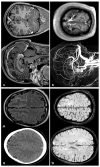

Spontaneous convexity subarachnoid hemorrhage (cSAH) is a vascular disease different from aneurysmal SAH in neuroimaging pattern, causes, and prognosis. Several causes might be considered in individual patients, with a limited value of the patient's age for discriminating among these causes. Cerebral amyloid angiopathy (CAA) is the most prevalent cause in people > 60 years, but reversible cerebral vasoconstriction syndrome (RCVS) has to be considered in young people. CAA gained attention in the last years, but the most known manifestation of cSAH in this context is constituted by transient focal neurological episodes (TFNEs). CAA might have an inflammatory side (CAA-related inflammation), whose diagnosis is relevant due to the efficacy of immunosuppression in resolving essudation. Other causes are hemodynamic stenosis or occlusion in extracranial and intracranial arteries, infective endocarditis (with or without intracranial infectious aneurysms), primary central nervous system angiitis, cerebral venous thrombosis, and rarer diseases. The diagnostic work-up is fundamental for an etiological diagnosis and includes neuroimaging techniques, nuclear medicine techniques, and lumbar puncture. The correct diagnosis is the first step for choosing the most effective and appropriate treatment.